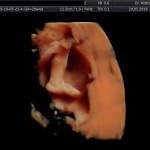

Modalidad de imagen ecográfica que permite evaluar, medir y capturar estructuras fetales superficiales e internas en 3 dimensiones (3D) y también en movimiento y en tiempo real (4D) con programas de realismo aumentado (HD LIVE) e imágenes tomografías fetales (TUI) mejorando significativamente la precisión en las mediciones fetales y la documentaciones de estructuras anatómicas.

Esta tecnología se puede utilizar desde la 6ta a la 40ma semana de embarazo.